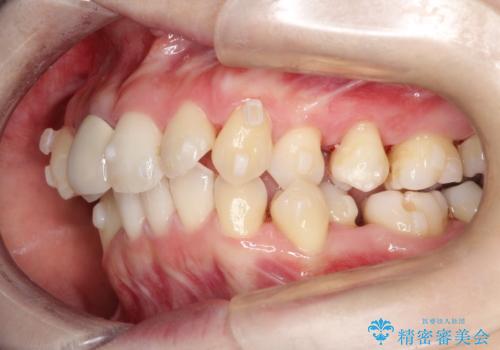

- 上下のがたつきを主訴に来院された患者様です。

上下の前歯と奥歯にがたつきがありました。

上下の奥歯を後方に移動させるのと、歯と歯の間をわずかに削ることでスペースを作り、歯を並べる計画としました。

比較的がたがたの度合いが大きかったですが、しっかりとマウスピースを使用していただけたので、順調に治療を終えることができました。